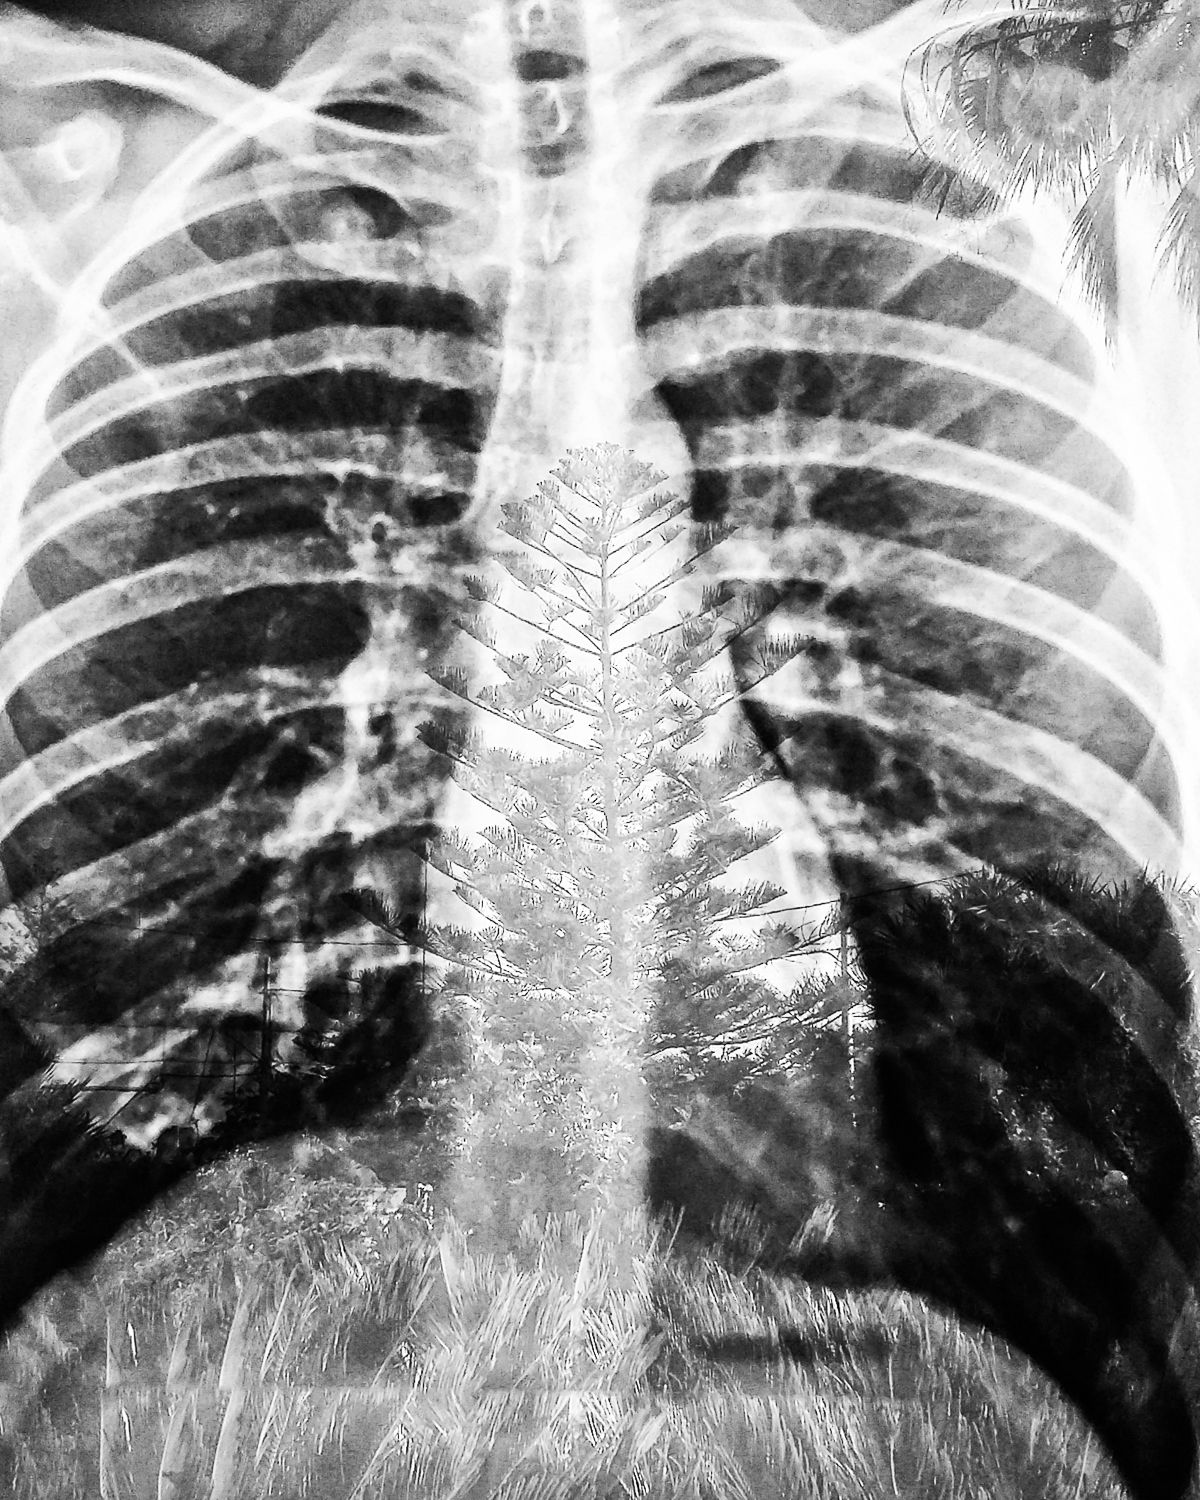

Surrender is a personal visual diary I collected during a deep and difficult moment of transformation I endured when faced with illness.

It is July 2016, 3 days after my 26th birthday, I wake up with a slight and growing ache in my right knee, till night when the pain becomes unbearable, it lasts several days and after few visits to the hospital the x-rays spot a suspicious mass on the upper tibia. It takes 2 months to get a wrong diagnosis and a consequent incorrect surgery, in hindsight making things worse. Ultimately I had to go to Pisa to cure what  revealed to be an osteosarcoma, a form of bone cancer. It is the 20th of December when Prof. Capanna implanted a Mega C, a prosthetic knee he designed and named after him, in my right leg. It takes 8 months before I can walk again and a couple of years of dealing with PTSD. Surrender is the memory diary of that struggle, of those days of pain in a static isolation observing the world from far. Surrender might be wrongly linked with losing hope although to me is quite the opposite, it is pure trust in the universe and whatever puts in your path, the only way for me to accept the concept of death and the surrealist situation I found or put myself in, transforming the trauma in lesson. It is the memory of this lesson that I wished to collect, even though I could not yet understand the lesson then, but I was hopeful the passage of time would transform the meaning of those images and I wanted to record my inner states so I might never forget those moments and the teachings that they together with the illness brought in my life.